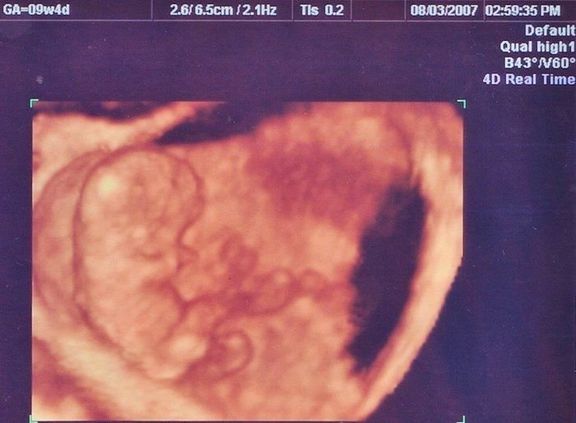

命の始まりは神秘的!2D・3D・4Dのエコー写真で見る「私と赤ちゃんの実録260日」 -

"おなかの中はどうなっていくの? エコー写真で振り返る、高齢ママのはじめての妊娠生活" -